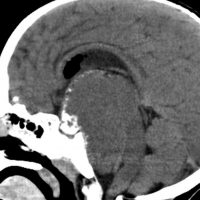

ちょっと大きな頭蓋咽頭腫です

嚢胞(液体が入っている袋)の部分と,腫瘍細胞が固まっている実質部分が入り交じっています。このくらいの大きさになってしまうと,下垂体機能を残すことはとても難しくなります。視神経が圧迫されて視力低下と視野障害を生じます。第3脳室が腫瘍で閉塞していて水頭症になっていますから知能の活動が低下します。

腫瘍を摘出するのに危ないのは,脳の血管の損傷です。左では白く,右では黒く線状に移っているのが太い脳動脈です。これら以外にもたくさんの細い重要な動脈が絡んでいます。

幸いこの患者さんの腫瘍は摘出できて患者さんは元気になりました。でもこのくらいのサイズになると手術がいつもうまくいくとは限りませんし重大な障害が残ることもあります。